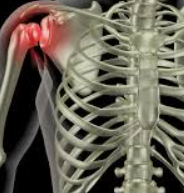

어깨탈구 원인

어깨탈구는 어깨 관절이 정상적인 위치에서 벗어나는 상태를 말합니다. 이는 어깨 관절을 구성하는 뼈, 근육, 인대, 힘줄 등이 손상되거나 약화됨으로써 발생할 수 있습니다. 어깨탈구의 가장 흔한 원인은 외상입니다. 넘어지거나 직접적인 충격을 받았을 때 어깨 관절이 강제로 움직이면서 탈구될 수 있습니다. 스포츠 활동 중에도 비슷한 상황이 발생할 수 있으며, 특히 충돌이나 반복적인 오버헤드 동작을 하는 스포츠에서 더 자주 보입니다.

또 다른 원인은 관절의 과도한 유연성이나 약화된 어깨 근육으로 인한 것일 수 있습니다. 이러한 경우, 갑작스러운 움직임이나 무리한 자세로 인해 탈구가 발생할 수 있습니다. 또한, 어깨 관절의 해부학적 구조상의 문제나 이전의 탈구 경험이 재발의 위험을 증가시킬 수 있습니다.

어깨탈구는 심한 통증과 함께 어깨의 움직임이 제한되는 것이 특징입니다. 탈구된 어깨는 의료 전문가에 의해 적절한 치료를 받아야 하며, 때로는 수술이 필요할 수도 있습니다. 예방을 위해서는 적절한 스트레칭과 강화 운동을 통해 어깨 근육을 튼튼하게 유지하는 것이 중요합니다. 또한, 위험한 활동을 할 때는 보호 장비를 착용하고, 안전 수칙을 준수하는 것이 좋습니다.